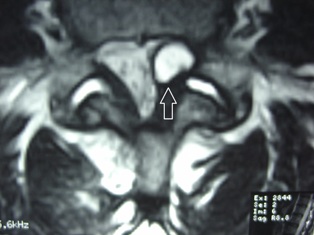

a synovial fluid-filled cyst that appears in the spine where facet joints degenerate. Synovial fluid is the lubricating fluid found in spinal joints.

Though relatively uncommon in causing spinal stenosis, the synovial cyst may cause pain, particularly in the over 65 year old patient. Synovial cysts are commonly found at the L4-5 facet joint area, causing pain into the low back, buttock, and maybe even leg. The cyst affects the spinal canal much like a disc herniation might, causing stenosis of the canal and pressure on the nerve roots.